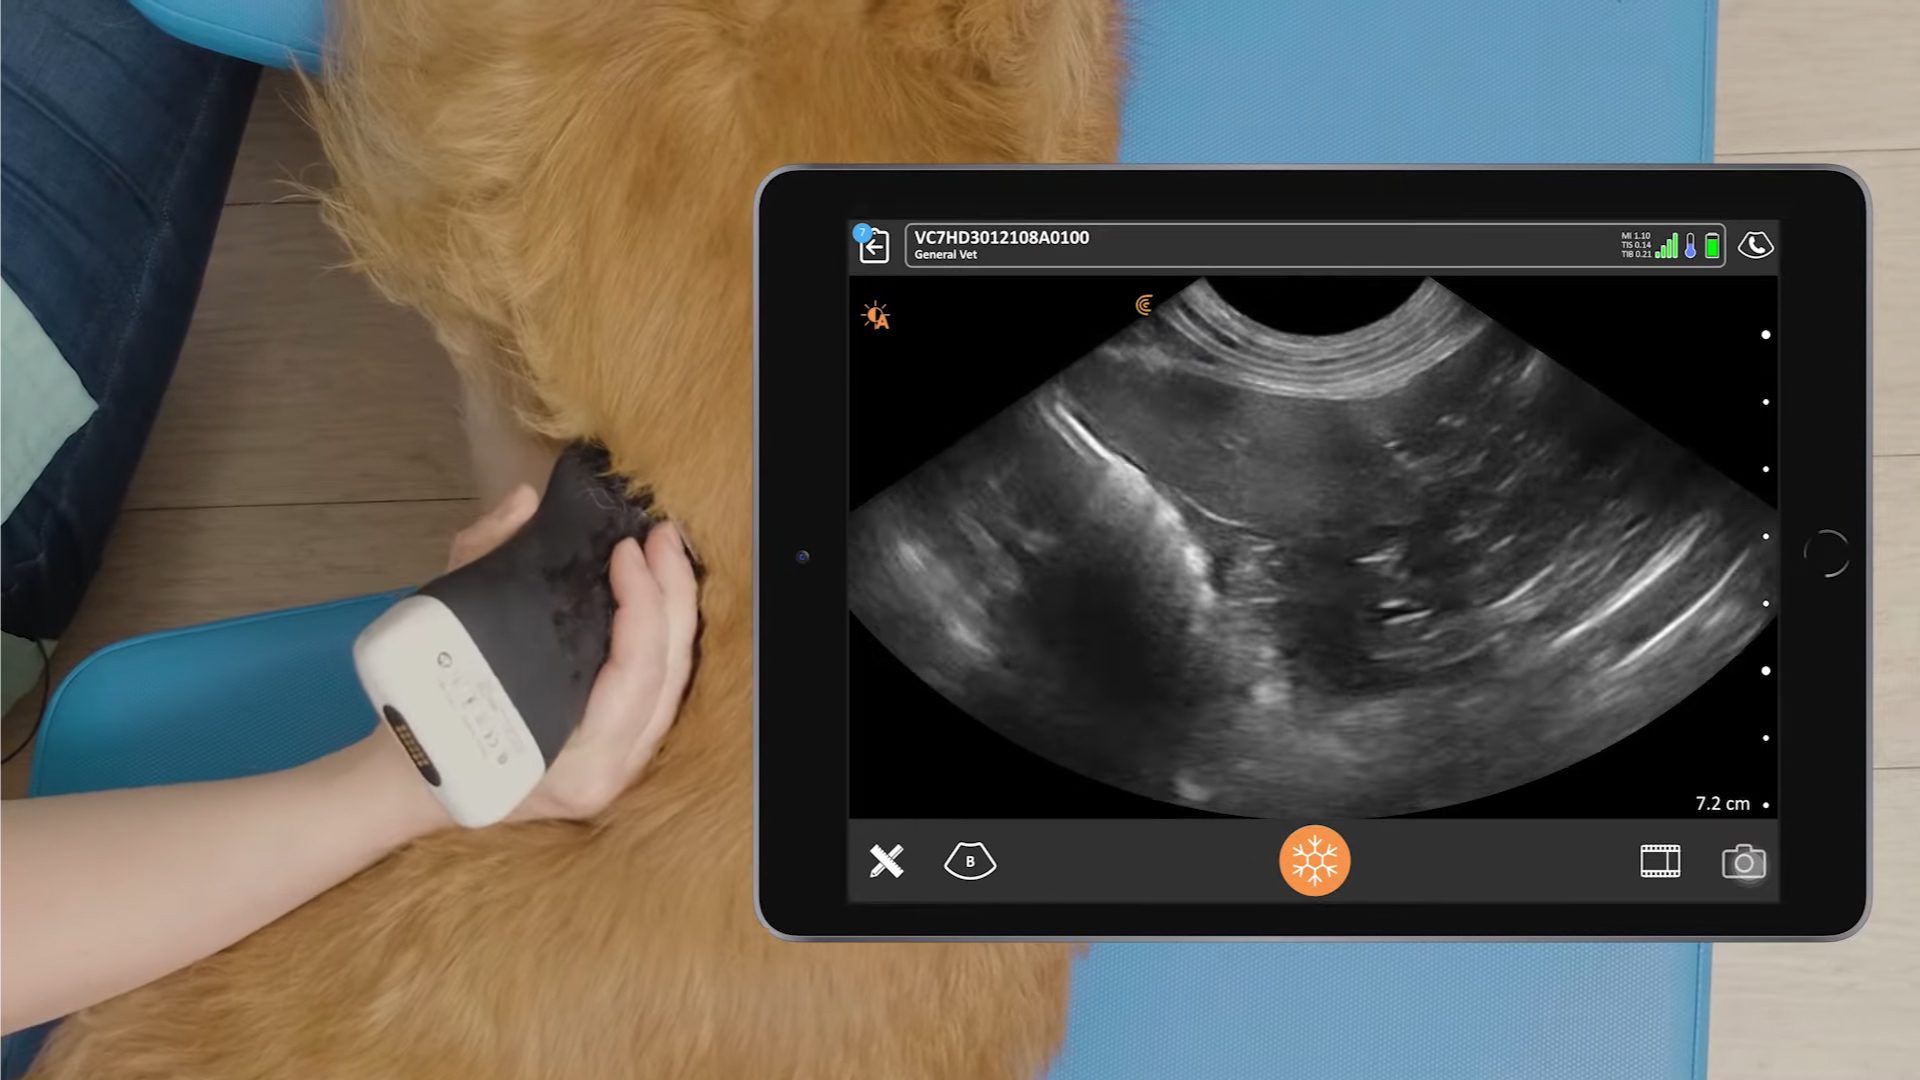

Dr. Camilla Edwards, DVM and founder of First Opinion Veterinary Ultrasound (FOVU) shared this case with us recently. The dog presented with rather vague symptoms, so Dr. Edwards proceeded with a thorough ultrasound examination of the abdomen and thorax.

History: 5-year-old male-natured Cockerpoo. 5 days of being unwell, some vomiting.

Ultrasound Findings: Visible organs appeared normal, and there was no free fluid seen in the abdomen or pelvis. The caudal vena cava was slightly enlarged, but this was thought to be because the dog was being over perfused.

In the thoracic views, there was normal lung sliding at multiple levels, no pleural fluid was present. The heart function appeared normal, but the heart was beating incredibly slowly, so an ECG was performed, revealing a heart block.

Watch the abdominal and thoracic ultrasound video:

Dr. Edwards uses the Clarius C7 HD3 Vet, which is specifically designed for clinical imaging of small and medium-sized animals. Our Advanced Veterinary Package offers more flexibility for users who need additional workflows for various animal exams.